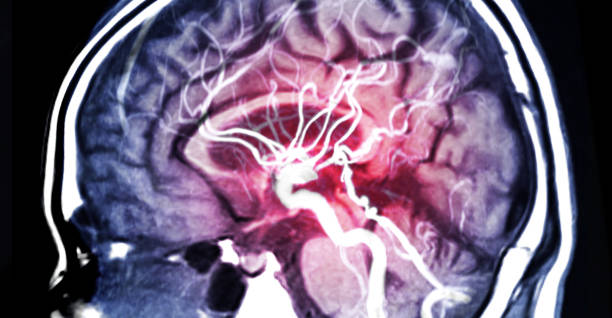

∎ 뇌동맥류 검사

최근 뇌동맥류 증상이 나타난다면

지체없이 병원에 방문하여

진단을 받아야 합니다.

신경과나 신경외과를 방문하여 검사를 받는데,

뇌 CT를 촬영하거나 MRI, 뇌혈관 조영술을 통해

질환을 확인합니다.

뇌동맥류 검사 상 정상적인 뇌동맥에서

비정상적으로 튀어나와 있는 혈관이 있으면

뇌동맥류로 진단을 받게 됩니다.